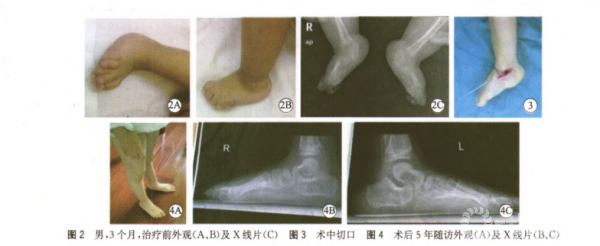

1.临床随访结果 所有病例微创手术前均行手法+石膏固定,术前平均更换石膏6次(5~10次),手术时平均年龄16.5个月(5~35个月),随访时间平均43.2个月(12~63.6个月),最近随访平均年龄3岁6个月(1岁9个月至6岁3个月)。3例4足经过石膏矫形获得距舟关节复位,行经皮跟腱松解和经皮钢针固定复位的距舟关节;其余13例26足距舟关节未获得一期距舟关节复位但脱位程度明显改善,行小切口切开复位距舟关节直视下钢针固定和经皮跟腱松解;3例5足术中因僵硬程度大跖屈、内翻<20°,行胫前肌、伸踇长肌、伸趾肌及外侧腓骨长短肌延长;术后28足伤口均愈合良好,2足(6.7%)拆除石膏时伤口有渗出,经过换药后愈合。最近一次随访示30足有良好外观,典型病例见图2-4,足内侧纵弓出现;背屈活动:术前/术后10°(0°~20°)/22.5°(5°~35°)(P<0.001),跖屈活动术前/术后-100(-20°~0°)/22.5°(5°~35°)(P<0.001),踝关节无明显功能障碍;足跟处于中和位5例9足,足跟外翻5°~8°的11例21足;2例3足(10%)术后1年随访发现有复发现象(跖屈活动<10°)站立位足跟有轻度外翻15°,摄片TAMBA35°,CAMBA10°,再次行石膏矫形4次后TAMBA10°,CAMBA5°,予以继续佩戴支具,同时白天穿垫足弓垫的矫形鞋。2例3足年龄大于4岁已终止矫形鞋只运用足弓垫。